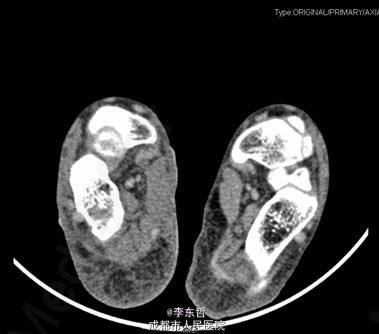

患者女,13岁4月,因“车祸致右足跟部皮肤撕脱伤清创缝合术后25天”入院。患者25天前因车祸导致右足疼痛流血伴功能障碍,右足跟部皮肤撕脱,遂到当地医院就诊,诊断为右足跟部皮肤严重剥脱伤,右跟骨骨折,右胫骨远端骨折。急诊下行“右足跟部皮肤严重剥脱伤清创缝合术”。术后给予止痛、消肿、预防感染等对症处理,目前右足外侧及跟部皮肤变暗,坏死。患者为进一步诊疗,故请我院远程会诊后转入我科继续治疗。患者病来精神、饮食可,大小便正常,体重未见明显改变。

查体:右足内踝、外踝及跟部皮肤变暗,部分缺血坏死。未见畸形,稍肿胀。触:右足趾皮温无明显降低,右足趾感觉未见明显异常。右足内踝、外踝及跟部皮肤局部压痛。动量:右踝关节活动受限,右踝关节活动诱发疼痛。右膝关节活动未见明显异常。 辅助检查:X线示:右跟骨骨折,右胫骨远端骨折。

初步诊断:1、右足跟部皮肤软组织撕脱伤清创缝合术后皮肤软组织大面积坏死伴感染;2、右跟骨骨折;3、右胫骨远端骨折;4、右足跖屈畸形。 处理:1、向患者及家属交待病情及注意事项。2、向上级医生汇报患者病情。3、完善相关术前等检查,择期行手术治疗。4、给予对症支持治疗。5、密切观察病情变化,根据病情及时处理。